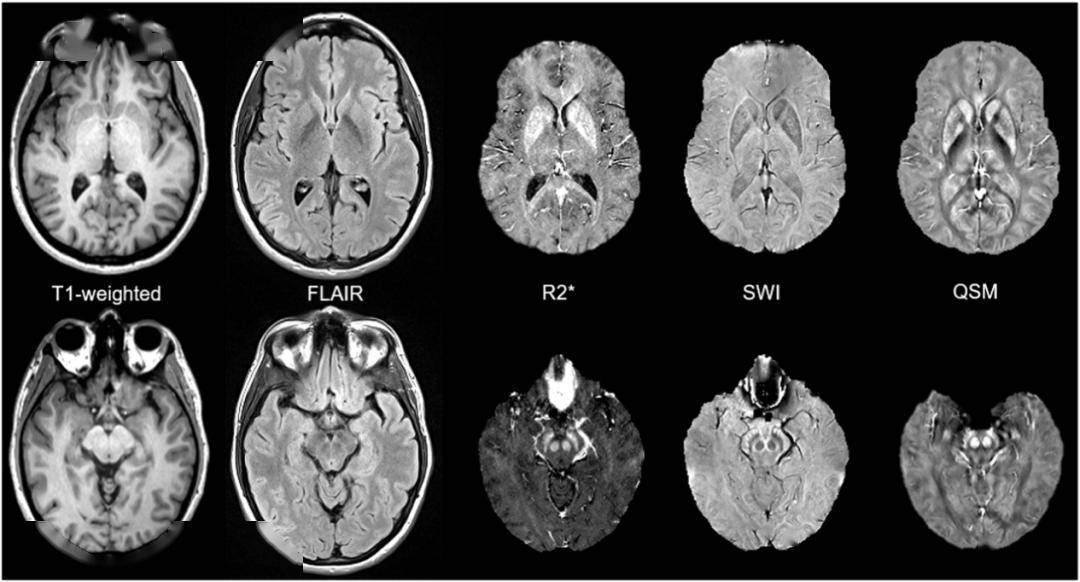

neuroimage磁共振3d梯度回波磁化转移序列同时对铁和神经黑色素进行

图片尺寸1270x714